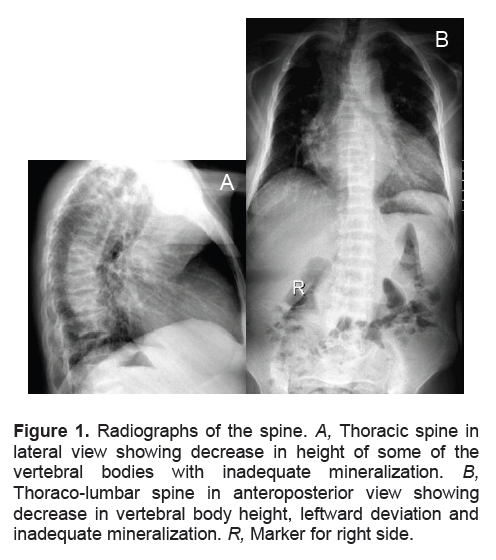

Skeletal x-rays showed compression deformities of the thoracic and lumbar vertebrae, thoraco-lumbar levoscoliosis with decrease in vertebral height and decrease in bone mineralization signifying osteopenia (Figures 1A and B). Pelvic x-rays revealed asymmetry of the pubic bone with non-delineation of the symphysis pubis, and irregularity of the left inferior pubic ramus, interpreted as a pathologic fracture.

Figure 1. Radiographs of the spine. A, Thoracic spine in lateral view showing decrease in height of some of the vertebral bodies with inadequate mineralization. B, Thoraco-lumbar spine in anteroposterior view showing decrease in vertebral body height, leftward deviation and inadequate mineralization. R, Marker for right side.